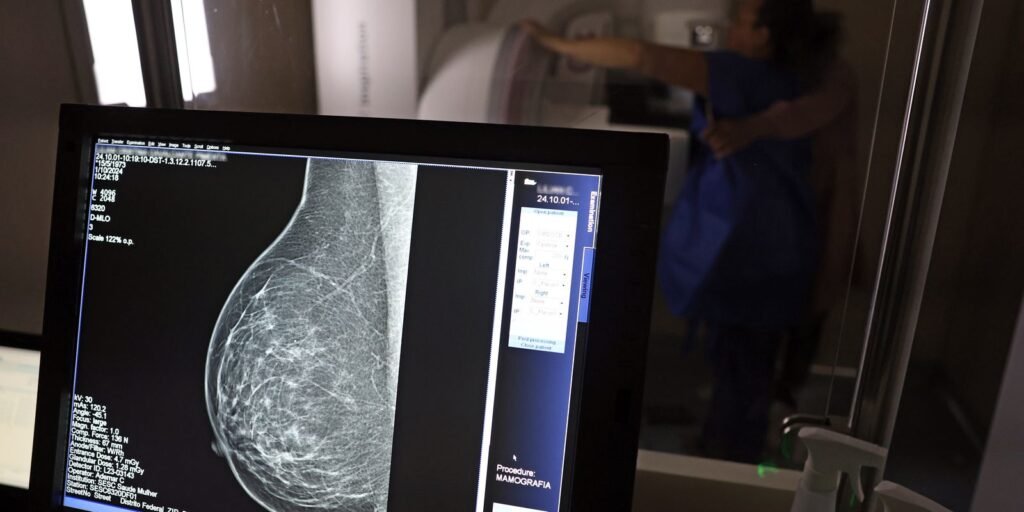

No Outubro Rosa, o Instituto Nacional de Câncer (Inca) estimou 73.610 novos casos este ano no país. É o câncer que mais mata mulheres no Brasil. As mulheres em tratamento pela doença têm o direito de receber o auxílio-doença ou o benefício de prestação continuada.![]()

A vice-presidente da Comissão de Previdência Social Pública da Ordem dos Advogados do Brasil do Rio de Janeiro (OAB-RJ), Danielle Guimarães, destaca que o câncer de mama é uma das doenças que mais afetam mulheres no Brasil, impactando não apenas a saúde física e emocional, mas também a capacidade de trabalho e a segurança financeira das pacientes.